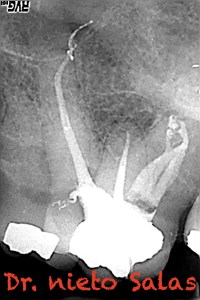

Os presento unos casos de varios molares superiores, con tres conductos mesiovestibulares con un foramen o con dos.

Una vez que tenemos medidas, obturamos los conductos:

No es habitual en nuestra práctica casos como estos, pero os pongo algunos más:

Sabemos que unas de las piezas que más fracasan, son estas piezas, pues, sin la ayuda de magnificación, es muy probable que dejemos alguna zona del sistema sin limpiar y mucho menos, obturarla.